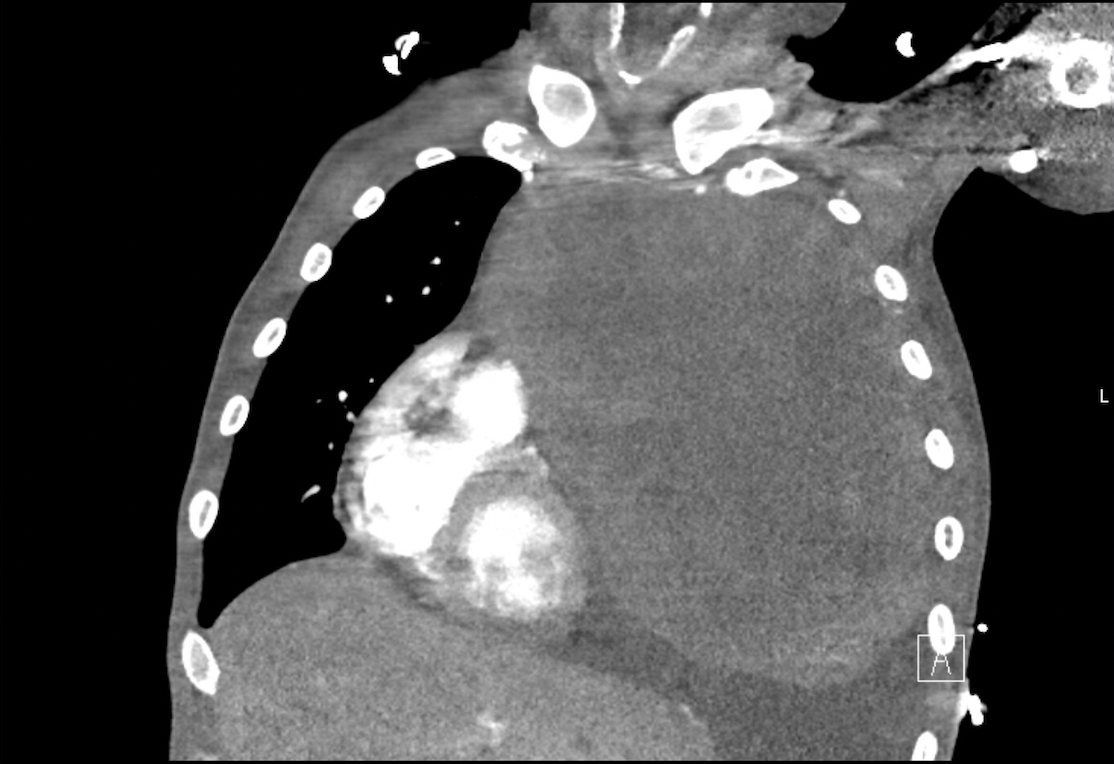

Abstract Body (Do not enter title and authors here): Primary mediastinal embryonal carcinoma is an exceptionally rare and aggressive extragonadal germ cell tumor, comprising less than 2% of mediastinal germ cell neoplasms. Cardiovascular complications, including pericardial effusion and tamponade physiology, are even more infrequent, with only isolated cases reported. We present the case of a 35-year-old male with no significant medical history who presented with progressive dyspnea, pleuritic chest pain, and right shoulder discomfort. Imaging revealed a massive anterior mediastinal mass (21.2 × 14.3 × 20.3 cm) compressing the left lung and shifting mediastinal structures rightward, with direct extension into the left atrium and pulmonary veins (Image 1 and 2). Echocardiography demonstrated a moderate-to-large pericardial effusion with right atrial inversion and respiratory variation in mitral inflow, suggestive of early tamponade (Image 3). However, due to stable hemodynamics and significant distortion of normal anatomy from the tumor mass, pericardiocentesis was deferred as high-risk. Multidisciplinary teams opted for conservative management, and the patient was initiated on systemic chemotherapy with ifosfamide, etoposide, and cisplatin. Serial imaging demonstrated stabilization of the pericardial effusion and early signs of tumor response. Pathology confirmed embryonal carcinoma with elevated tumor markers (AFP 514 ng/mL, β-hCG 158 mIU/mL, LDH 3,078 U/L). Neurological evaluation for multifocal infarcts revealed a brain metastasis and suspected embolic phenomena; vascular imaging showed a left popliteal artery thrombus. The case illustrates a rare instance where both malignant pericardial effusion and external tumor compression contributed to tamponade physiology without overt clinical collapse. It highlights the complexity of managing cardiac involvement in malignancy, where anatomy, mass effect, and clinical stability guide intervention. This case reinforces the need for individualized cardiovascular decision-making and interdisciplinary coordination in rare oncologic presentations involving pericardial pathology.